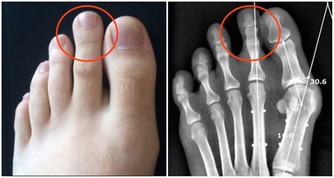

(2)骨質疏鬆